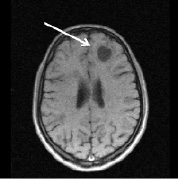

Информация о диссеминированном рассеянном энцефаломиелите